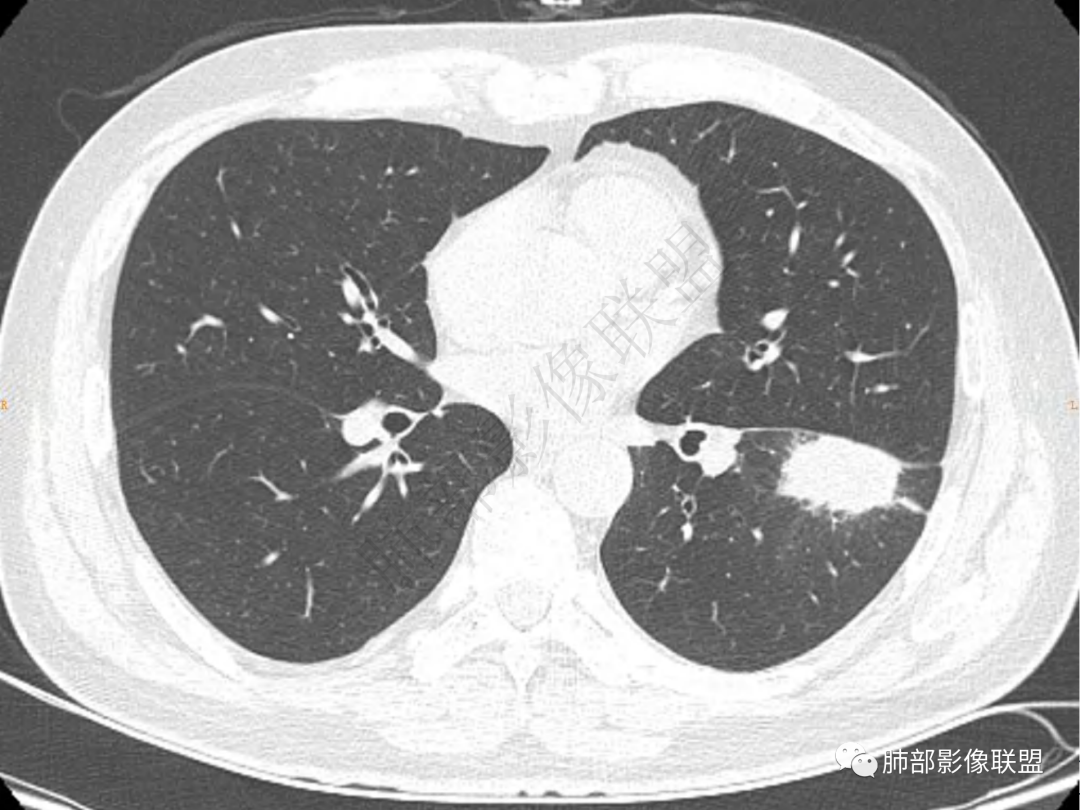

2.左肺下叶团片影,跨背段及内前基底段,实性部分类椭圆形,密度不甚均匀,可见毛刺及棘状突起,未见典型分叶及胸膜凹陷。病灶上下缘可见相应肺段支气管旁进侧出,管壁轻度增厚,未见狭窄阻塞。

3.周边较大范围磨玻璃影,边界相当模糊,小叶增厚明显。注意叶裂另一侧、左肺舌段亦可见磨玻璃影及增厚的小叶间隔。未见明确卫星病灶。

1.病灶不够密实,没有典型分叶,收缩乏力等,支气管未见截断等,缺乏一般肿瘤性肿块特征。

2.周围磨玻璃影边界不清缺乏限制,甚至“激惹”到相邻肺叶,也许提示较明显的炎性水肿。